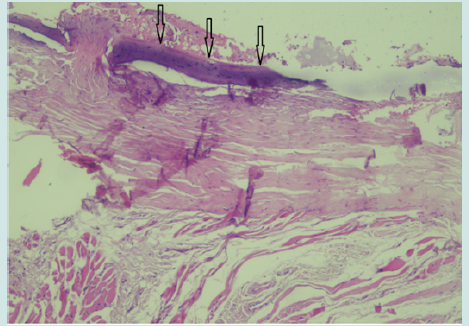

A 5-year-old boy presented with troublesome discharge, tenderness, and redness in front of his neck. An operation had been performed for TDC at another clinic a year ago, records of which were not available. He had the history of midline neck abscess three times since that. The rest of his medical history was unremarkable. Following the resolution of the infection with antibiotic treatment, physical examination revealed a cystic swelling which situated below the hyoid in the midline. It is harder than the TDCs that we treated before. Fixation to surrounding tissues was not let to movement of the mass with deglutition and tongue protrusion. Thyroid gland was normal by palpation. Ultrasound scan of the neck showed a subpharyngeal subcutaneous cyst in size of 24x12 mm with anechoic content located below the hyoid bone. No calcifications or mural nodules were noted in the cyst. There was no significant cervical lymphadenopathy. The thyroid gland was normal. A standard Sistrunk procedure was performed with resection of the cyst in continuity with the central section of the hyoid bone and excision of the duct up to foramen caecum for recurrent TDC. The histopathological findings confirmed fibrocartilages tissue and calcified cyst wall (Figure 1). No malignant cells were seen. Lymphocytes and plasma cells were reported. The cyst was interpreted as calcified benign TDC. The patient had an uneventful postoperative course. Two-year clinical follow up is uneventful without any complication or recurrence.

Figure 1: Microscopic examination revealed calcified cyst wall (arrow) with lymphocytes and plasma cells (hematoxylin-eosin, x 100).